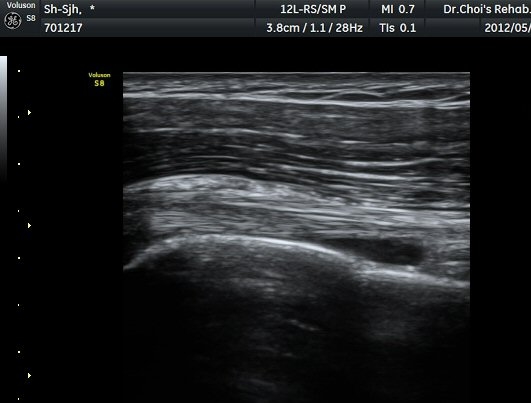

°Ë»ç¿¡¼­ Ç÷·ùÁõ°¡°¡ °üÂûµÈ´Ù(»çÁø 2). À̵ιڱ٠Á¾´Ü¸é°Ë»ç¿¡¼­µµ °Ç ÁÖÀ§ ¼ö¾×Àú·ù°¡ È®ÀÎ

µÈ´Ù(»çÁø 3). ±Ø»ó°Ç Á¾´Ü¸é°Ë»ç»ó ±Ø»ó°Ç ºÎÂøºÎ¿¡ °í¿¡ÄÚ µ¢¾î¸®°¡ °üÂûµÇ°í(»çÁø 4, 5)